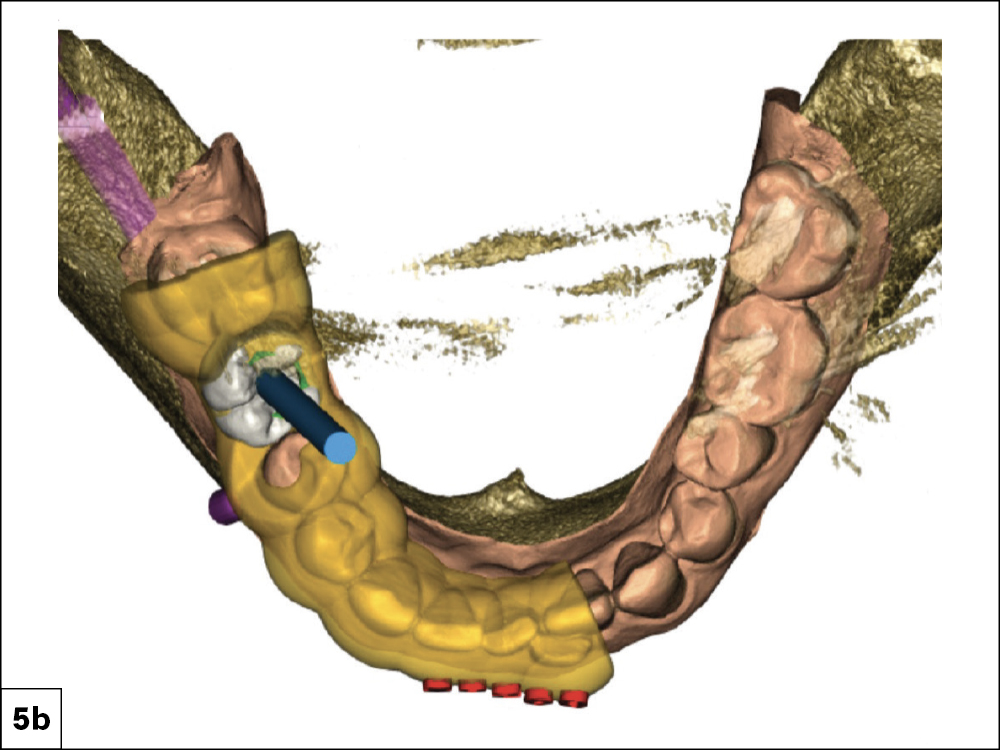

Occlusal View Which Indicates the Placement of the Surgical Guide

Detailed Surgical Report Revealing Distance to Vital Structures

Figures 5a, 5b: An occlusal view clearly indicated the placement of the surgical guide and confirmed the trajectory the implant would follow as well as the position of the access hole on the occlusal surface. The detailed surgical report included a cross section revealing the implant’s proximity to vital structures. I could see the outline of the crown, the access channel, the outline of the implant (in blue), and the inferior alveolar nerve canal (in purple). I noted the distance between the implant and the nerve canal as well as the lingual concavity, another very important landmark when placing implants. To avoid complications, the plan maintained a safety zone of at least 2 mm.